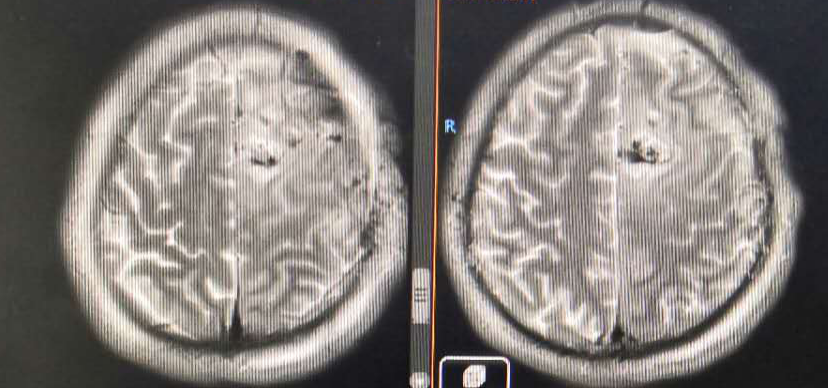

复查MRI提示:局部病灶强化,PWI提示局部灌注有缺失,考虑病情进展,同时不除外假性进展,患者脑水肿范围较大。

根据以往经验调整治疗方案:1、根据复发胶质瘤相关指南,首选抗血管生成药治疗;2、MDT讨论:病灶累积胼胝体,再次手术难度大;3、给予“阿帕替尼425mg qd po”。之后显示水肿变小,灌注降低。继续原方案治疗。

8月份复查再次显示肿瘤进展,由于没有更好的治疗方案,所以暂时继续原方案治疗。

从影像学看该患者是弥漫星形细胞瘤WHO II级,但该患者DWI上呈稍高信号,增强扫描却未见强化,而肿瘤的强化与其级别并非完全成正比,因此推测该病例具有胶质母细胞瘤的特点,WHO分级等同于 IV级。